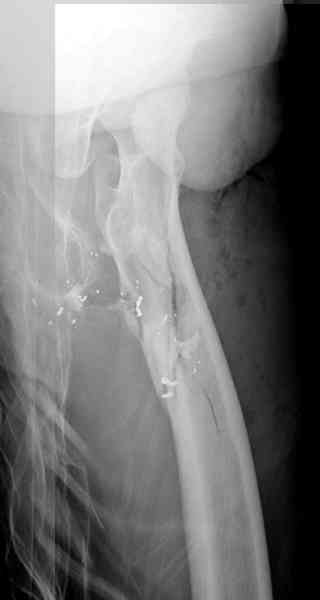

В приложении пример огнестрельного ранения бедра, оперированного на 2 сутки после ранения.

Штифтование было выполнено только на вторые сутки по причине задержки перевода из другого госпиталя, АБ профилактика была начата в другом учреждении, с момента госпитализации пациента к ним. Входное пулевое отверстие и зона введения штифта зажили первичным натяжением.

В конце 90-ых попалось несколько статей по nail exchange procedures in treatment of posttraumatic osteitis и решился попробовать на огнестрельных переломах, которые до этого лечил по полной схеме:расширенный дебрайдмент+ внешняя фиксации+промывные системы с антибиотиками и без антибиотиков в промывной среде. Всё заканчивалось длительной госпитализацией, плохими функциональными результатами( страдала функция колена), необходимостью повторной хирургией - отсроченная внутренняя фиксация переломов, длительной реабилитацией. На гвоздях процесс пошел лучше: остеомиэлитов не было и больные мобилизовывались быстрее.

Единственно что наблюдал - замедленная консолидация, судя по серийным Рг граммам. В приведенном случае прии вялом мозолееобразовании сделал ошибку, решившись динамизировать гвоздь - перелом сросся со значительным укорочением бедра - повторная хирургия по удлинению бедра и проксимальным запиранием, больной мобилизован и вполне доволен(кстати заметить больной с ВИЧ инфекцией - изначально скомпрометированный иммунитет и несмотря на это, всё прошло без костной и мягкотканной инфекции.